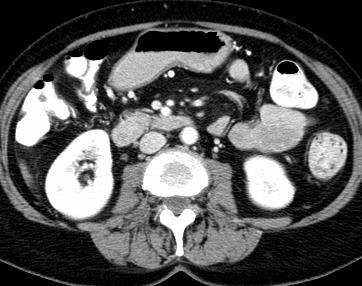

Due to the constraints of the imaging device and high cost in operation time, computer tomography (CT) scans are usually acquired with low intra-slice resolution. Improving the intra-slice resolution is beneficial to the disease diagnosis for both human experts and computer-aided systems. To this end, this paper builds a novel medical slice synthesis to increase the between-slice resolution. Considering that the ground-truth intermediate medical slices are always absent in clinical practice, we introduce the incremental cross-view mutual distillation strategy to accomplish this task in the self-supervised learning manner. Specifically, we model this problem from three different views: slice-wise interpolation from axial view and pixel-wise interpolation from coronal and sagittal views. Under this circumstance, the models learned from different views can distill valuable knowledge to guide the learning processes of each other. We can repeat this process to make the models synthesize intermediate slice data with increasing inter-slice resolution. To demonstrate the effectiveness of the proposed approach, we conduct comprehensive experiments on a large-scale CT dataset. Quantitative and qualitative comparison results show that our method outperforms state-of-the-art algorithms by clear margins.